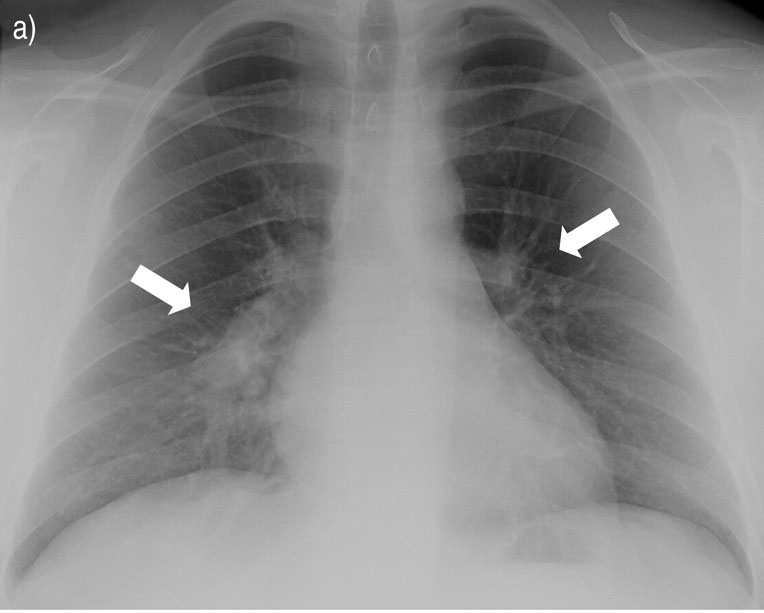

The rheumatologic diagnosis most often responsible for the findings shown by the arrow.

What is Sarcoidosis.